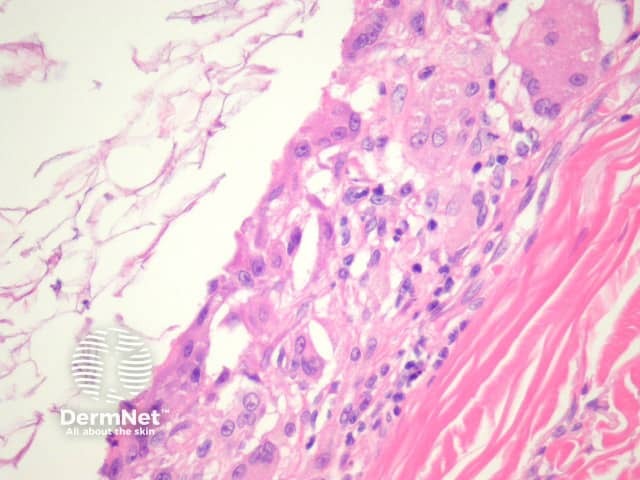

Sections of an epidermoid cyst show a cystic structure occupying at least the upper dermis but larger lesions may grow to involve the entire dermis (figure 1). They are usually unilocular but are rarely multilocular. The lining of the cyst is composed of an epithelium which is flattened and contains a granular layer of keratohyaline granules (figures 2, 3). The cyst lining is similar to the surface epithelium but lacks rete ridges which are seen in the overlying epidermis (figure 4, arrow).

The keratin contained in the cyst is lamellated and acellular (figure 7).

Figure 3

Figure 4